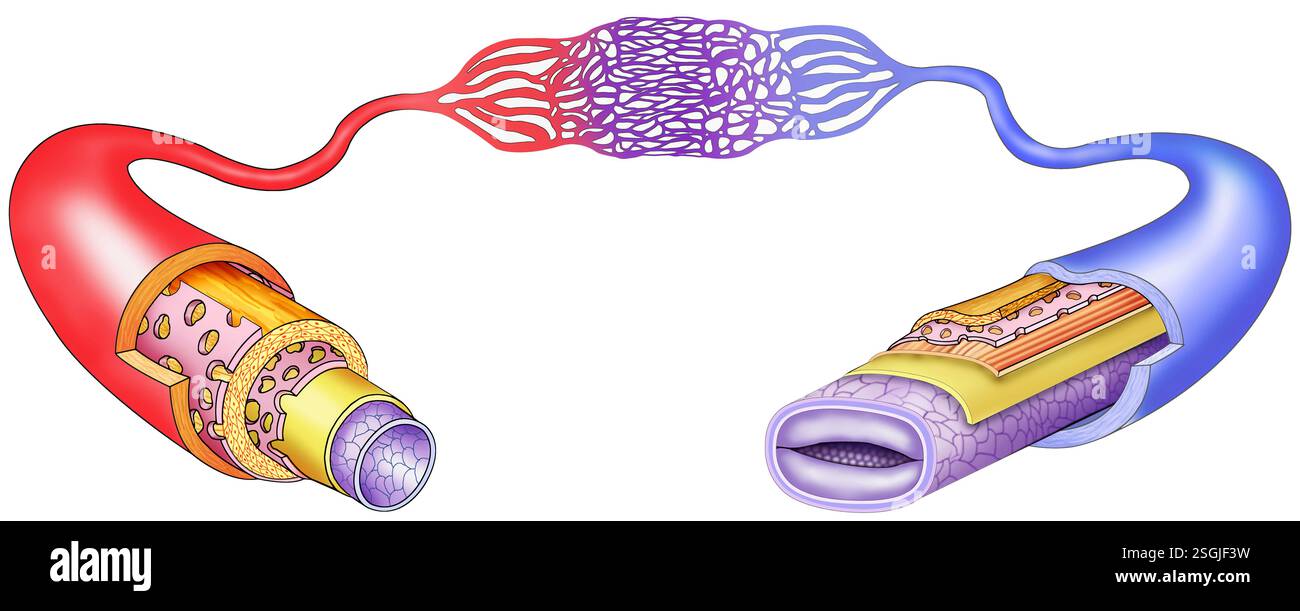

Diagram of layers of veins and arteries. These transport blood, oxygen, nutrients and waste through the heart, arteries, veins and capillaries. Stock Photohttps://www.alamy.com/image-license-details/?v=1https://www.alamy.com/diagram-of-layers-of-veins-and-arteries-these-transport-blood-oxygen-nutrients-and-waste-through-the-heart-arteries-veins-and-capillaries-image647025117.html

Diagram of layers of veins and arteries. These transport blood, oxygen, nutrients and waste through the heart, arteries, veins and capillaries. Stock Photohttps://www.alamy.com/image-license-details/?v=1https://www.alamy.com/diagram-of-layers-of-veins-and-arteries-these-transport-blood-oxygen-nutrients-and-waste-through-the-heart-arteries-veins-and-capillaries-image647025117.htmlRF2SGJF3W–Diagram of layers of veins and arteries. These transport blood, oxygen, nutrients and waste through the heart, arteries, veins and capillaries.